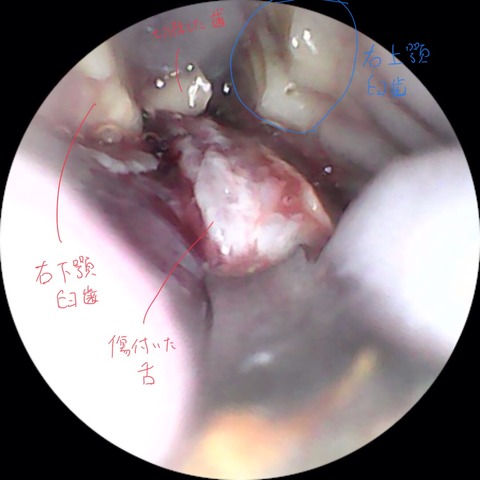

⇩臼歯(奥歯)が不正咬合により過長し、舌や頬の粘膜を傷つけてた症例